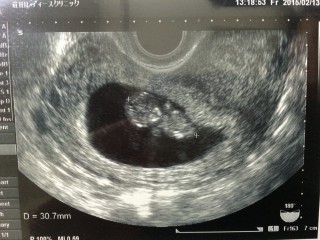

10w2d34.2㎜ 1週間前で、1㎝も成長してくれてました! 寝返りをうつ様なしぐさがと~ってもかわいい。4D画像は手足がくっきりと写し出されていていないいないばぁをしてるようでした。 こんなに小さなからだの力強く動く心臓の音、感動します、すくすく大きくなってね♪

34.2mmで順調に大きくなってくれています☆エコーでは手を動かして指まで吸っていました!!愛おしいです!!早く会いたい(;_;)笑